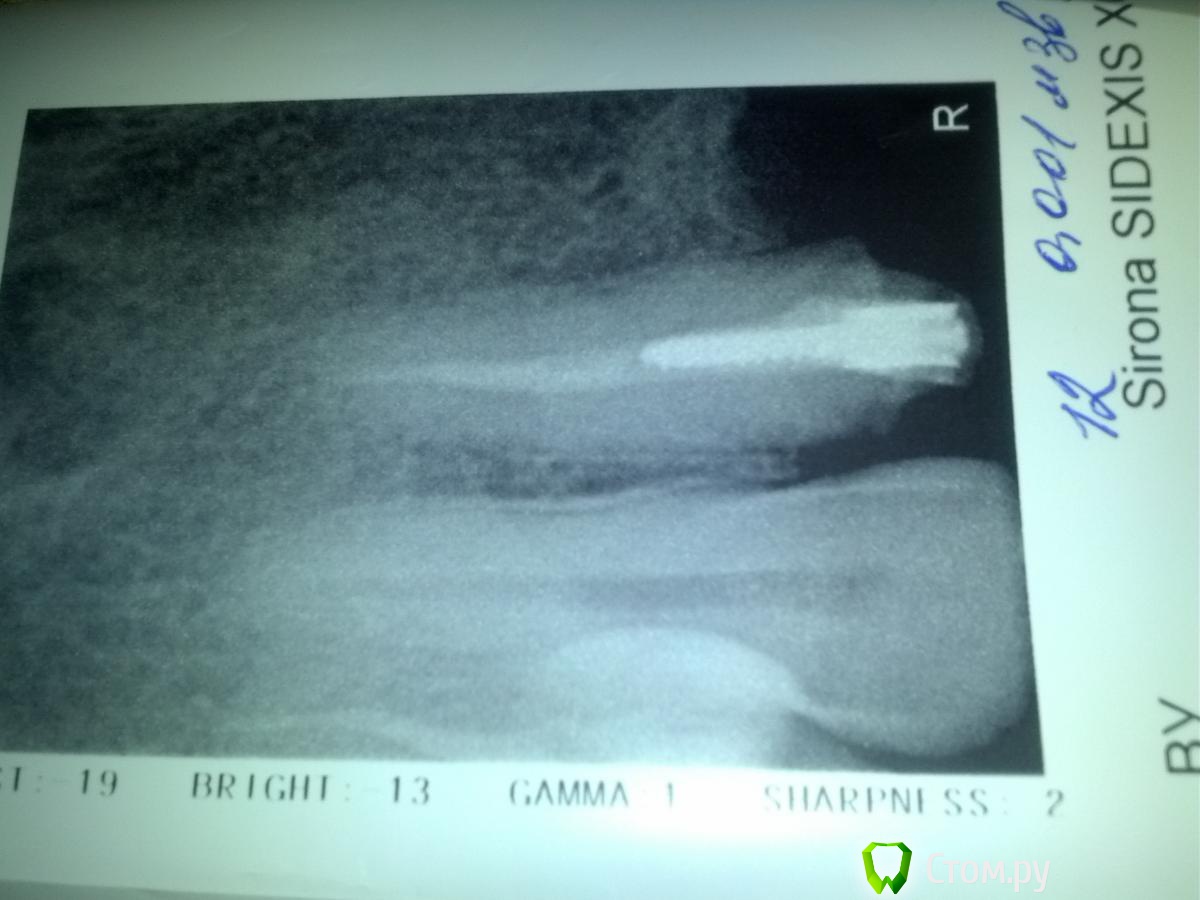

bogu Опубликовано 11 марта, 2014 Поделиться Опубликовано 11 марта, 2014 (изменено) Сняла металлокерамику, которая простояла 11 лет, из-за нарушения эстетики (начала появляться метал.полоска между десной и коронкой), решила поставить цирконий, сняли коронки, врач рекомендовал поменять пломбы и увеличить коронковую часть, т.к. под металлокерамику было сильно обточено. Терапевт говорит, что коронковая чать у зубов разрушена и стекловолокно ставить нет смысла, может обломиться, настаивает на вкладках, врач-ортопед, говорит, что вкладка из диоксида циркония не будет амортизировать и может треснуть, тогда ее уже не достанешь.(хотя судя по всему финансово должен был бы быть заинтересован во вкладках . в зубах стоят штифты металлические, один сегодня достали, пока накрыли врем пломбой-не знаю что делать...Зубы передние резцы и клык (5 ед). До этого 11 лет стоял мост, сейчас хотела поставить отдельные.. Посоветуйте, какие варианты есть... На КТ каналы заполнены, а сегодня на визиографе есть некоторые чуть светлее участки, как терапевт сказала, не пустота, но неравномерно паста лежит..(не знаю, видно ли будет на фото) что делать? оба врача высказали свои мнения, к одному решению не пришли, ответственность за решение переложили на меня(( Клиника где протезируюсь, одна из лучших в городе Изменено 11 марта, 2014 пользователем bogu Ссылка на комментарий

bogu Опубликовано 11 марта, 2014 Автор Поделиться Опубликовано 11 марта, 2014 Выложила Ссылка на комментарий